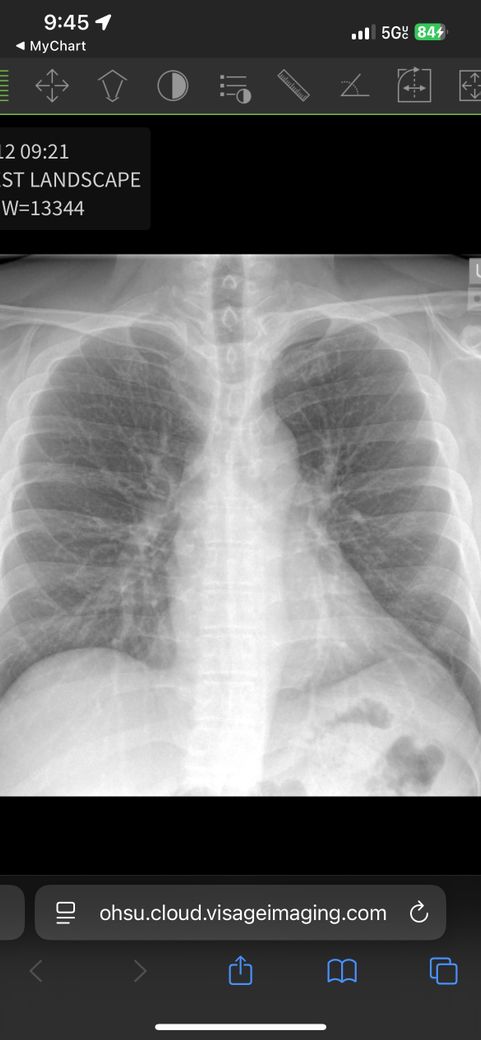

미국에서 흉부 통증으로 urgent care 방문후 엑스레이 촬영했는데 사진 확인부탁드립니다

명치주변 그리고 위쪽으로 쥐는듯한 통증이 있어서 폐암이 무서워서 급한대로 urgent care에서 흉부 엑스레이 촬영 및 피검사를 했고 문제가 없다고 하는데…. 어전트케어에는 보통 수간호사가 의사 역활을 해서 사진에 이상이 있는지 확인하고 싶습니다. 오른쪽 위 쇄골쪽 동그란 형태? 그리고 중앙에 하얀색으로 점처럼 보이는게 괜찮은건가요?… ct 촬영을 하려면 반년을 기다려해서 걱정입니다

올려주신 흉부 엑스레이 사진에서 특별한 이상 소견은 관찰되지 않습니다.

오른쪽 위 쇄골쪽 동그란 형태는 1번 갈비뼈 사이의 공간을, 중앙에 하얀색 점처럼 보이는 부위는 폐혈관을 말씀하시는 것 같습니다.

사진으로 찍어올려주신 엑스레이만 가지고는 사실 정확한 판단은 어렵지만 보이는 범위 내에서는 특별한 이상이 있어 보이지는 않습니다.

명치 주변의 쥐어짜는 듯한 통증이 발생할 때는 역류성위식도염을 가장 먼저 의심해 볼 수 있겠으나 심장질환도 감별이 필요합니다. 안타깝게도 이 두 질환 모두 엑스레이로는 진단이 불가한 질환들입니다.